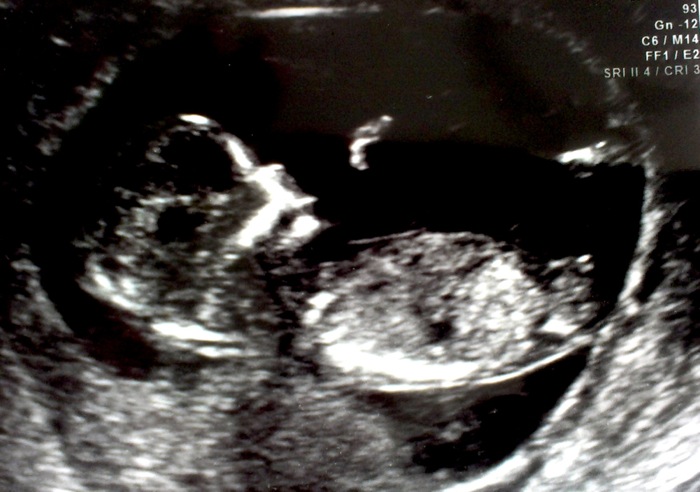

This was at 12.5 weeks.

here's a nub close up...